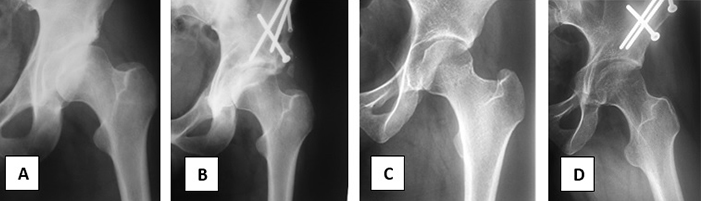

Figura 4

A- Mujer de 33 años de edad, ángulo de Wiberg de 3°, atrosis 2 de Tönnis y geoda supra acetabular.

B- 6 meses postcirugia con injerto óseo molido en la geoda y en la osteotomía del Iliaco. Wiberg de 37°.

C- Varón de 19 años de edad. Ángulo de Wiberg preoperatorio 19° y lesión tipo Cam.

D- 2 años de Wiberg de 29° y Cam resecado.